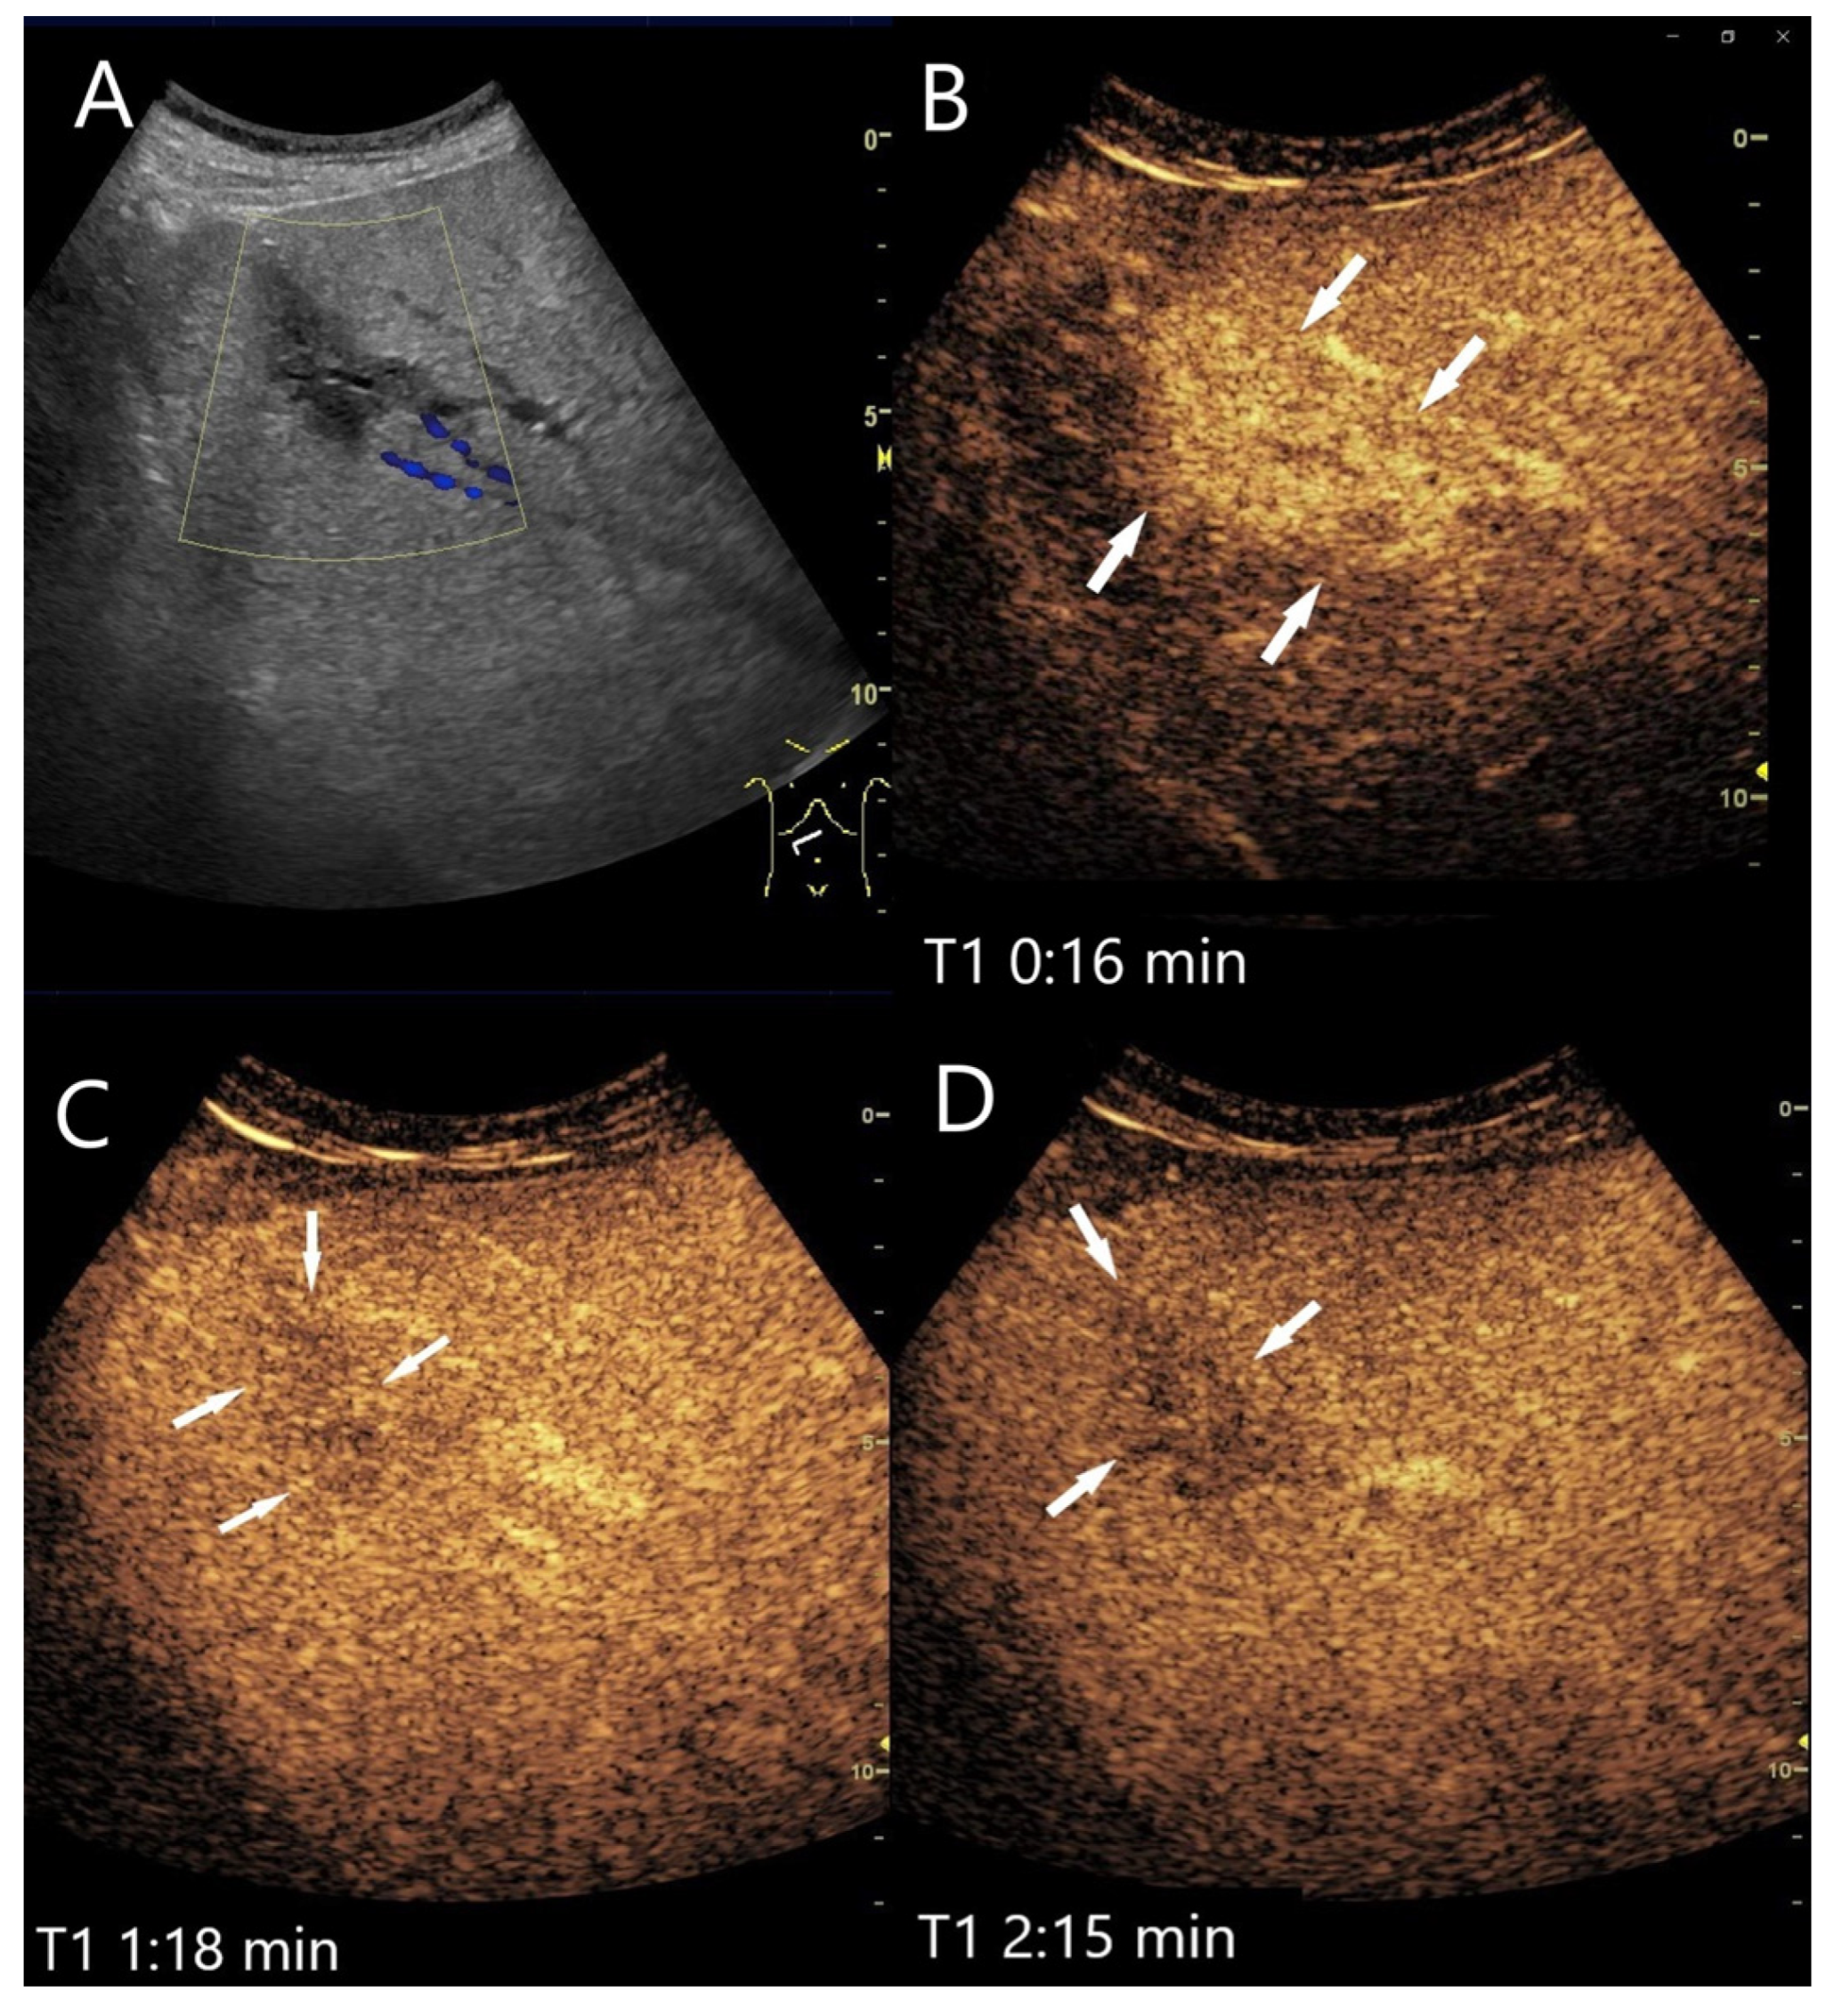

Figure 5.

FNH/nodular regenerative hyperplasia newly diagnosed in follow-up care after colon carcinoma and adjuvant chemotherapy with capecitabine and irinotecan. Initially, the lesions with a size up to 30 mm showed a wheel-spoke-like homogeneous hyperenhancement in the AP with isoenhancement in the PVP and LP. Over time, however, hypoenhancement developed in the LP. The images show the lesions three years after the initial diagnosis: the lesions (between the markings) are slightly larger (A). CEUS (B) and parametric imaging (C) show a typical wheel-spoke-like enhancement. In parametric imaging (C), the time of enhancement is displayed in different colors. The lesion is homogeneously hyperenhanced in the AP, a central scar is visible (D). In the LP, the lesions (arrows) are hypoenhanced with emphasis on the central parts (E,F). These lesions were, therefore, not clearly classifiable as benign, particularly in a patient with a history of colon carcinoma. A US-guided biopsy is performed. This revealed findings compatible with FNH and no evidence of metastases.